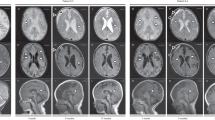

Biotin, pantothenate and lipoate-dependent metabolic pathways and the effect of identified variants in SLC5A6. a Pedigree of the non-consanguineous family. b Chromatograms from Sanger sequencing of patient DNA compared to cDNA show decreased expression of the V141Afs*34 allele and stable expression of the R400T allele. c Uptake of radiolabelled biotin by HeLa cells transfected with empty vector, wild-type or mutant SMVT expression constructs. Uptake by mutant constructs is decreased compared to wild-type (p = 0.008) and not significantly different to empty vector (p > 0.05). Data show the mean and standard error of the mean (n = 4). d SCL5A6 function and e Enzymes for which the vitamins Biotin (green), Pantothenate (blue) and Alpha-lipoic acid (red) play a role as important cofactors in: the degradation pathways of the amino acids leucine, isoleucine, valine and glycine; glucose energy metabolism; the TCA cycle; and fatty acid oxidation metabolism. All pathways apart from the glycine cleavage system play a fundamental role in cellular energy production. The pathways involved with fatty acid metabolism and branch chain amino acid breakdown occur almost exclusively in the liver. BBB blood–brain barrier, BCKD Branch chain ketoacid dehydrogenase, CNS central nervous system, KDHC ketoglutarate dehydrogenase complex, PC pyruvate carboxylase, PCC propionyl-CoA carboxylase, PDHC pyruvate dehdrogenase complex, 3MCCC 3-methyl crotonyl-CoA carboxylase